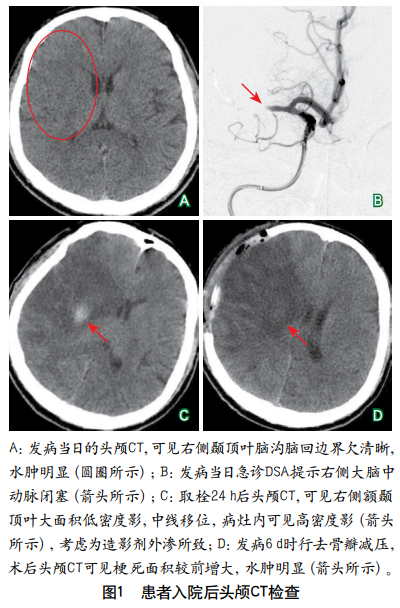

伴皮质下梗死和白质脑病的常染色体显性遗传性脑动脉病患者大脑中动脉闭塞血管内治疗1例并文献复习

摘要:伴皮质下梗死和白质脑病的常染色体显性遗传性脑动脉病(cerebral autosomal dominant arteriopathy with subcortical infarcts and leukoencephalopathy,CADASIL)是NOTCH3基因突变所致的遗传性脑小血管病,主要病变血管为颅内小动脉,累及大脑皮质和颅内大/中动脉的报道较罕见,目前缺乏特效治疗方法。本文报道